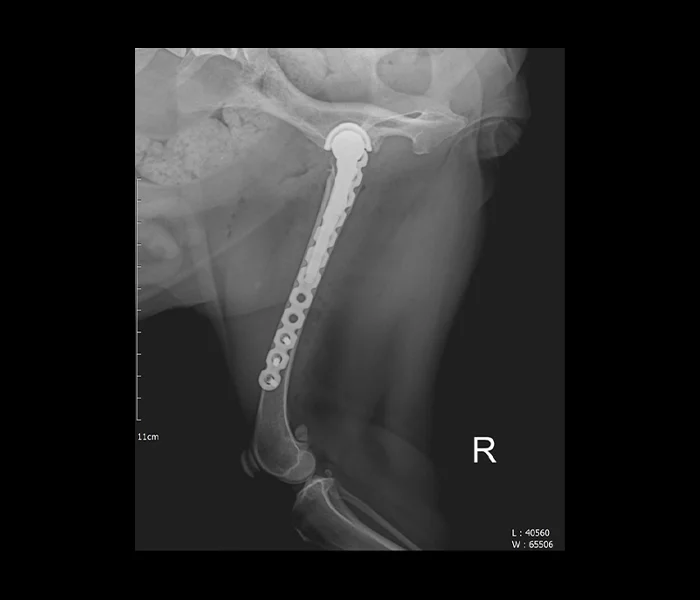

리본동물의료센터 인공관절

3D 프린팅 기반 맞춤형 임플란트 설계로

고정력 높은 인공관절 수술을 제공합니다.

우리 아이가 관절 문제로 심한 파행과 통증을 겪고 있나요? 리본동물의료센터

인공관절센터는 정형외과 전문 의료진과 '3D 프린팅 기반 맞춤형 임플란트 설계' 시스템을

갖춘 고난도 인공관절 수술 전문 센터입니다.

인공 고관절 치환술(THR)과 인공 활차구 치환술(PGR)에서 아이 개별 체형에 딱 맞는

임플란트를 적용하여 고정력을 높이고 재발 위험을 최소화합니다.

정밀 진단부터 수술, 마취, 재활까지 통합 케어를 통해 아이가 통증 없이 걷는 삶을 되찾도록 돕습니다.